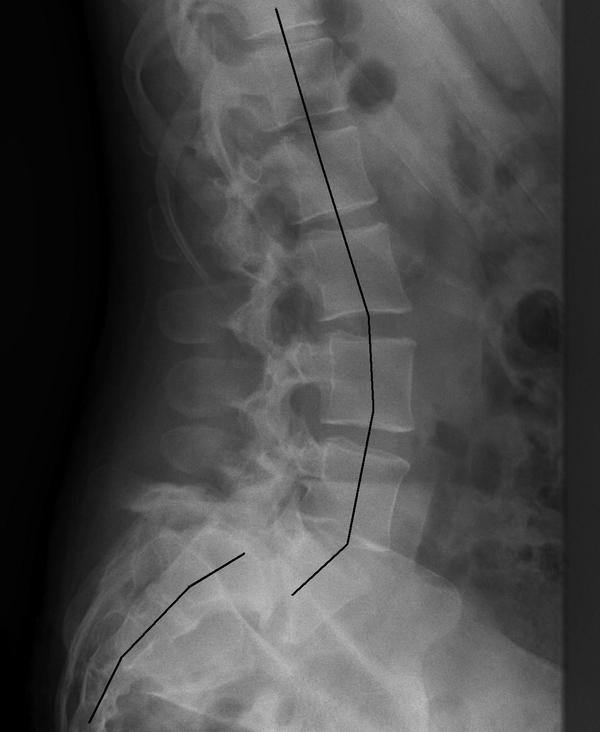

Defeitos da Pars - Espondilólise e Espondilolistese

Espondilólisee espondilolistese são lesões da coluna lombar relativamente comuns em atletas e geralmente ocorrem no segmento lombar (L5-S1) em atletas jovens envolvidos em esportes com hiperextensão repetitiva e carga axial.

De fato, quase 40% dos atletas com dor nas costas com duração de mais de 3 meses apresentam alterações das pars interarticularis na coluna lombar.

Os sintomas apresentados são dor lombar exacerbada por extensão, geralmente, sem irradiação.

Em casos de escorregamento grave, um abaulamento pode ser palpável; caso contrário, o exame físico pode revelar contraturas e espasmo muscular lombar. Exames de imagem devem incluir radiografias e tomografia computadorizada. O grau de deslizamento, se for o caso, pode ser determinado utilizando as radiografias.

A tomografia computadorizada é a modalidade de escolha para definir a arquitetura óssea das pars. O uso de PET-Scan pode permitir a detecção de fraturas “stress” ocultas e agudas se filmes de raio-x simples não revelarem um defeito.